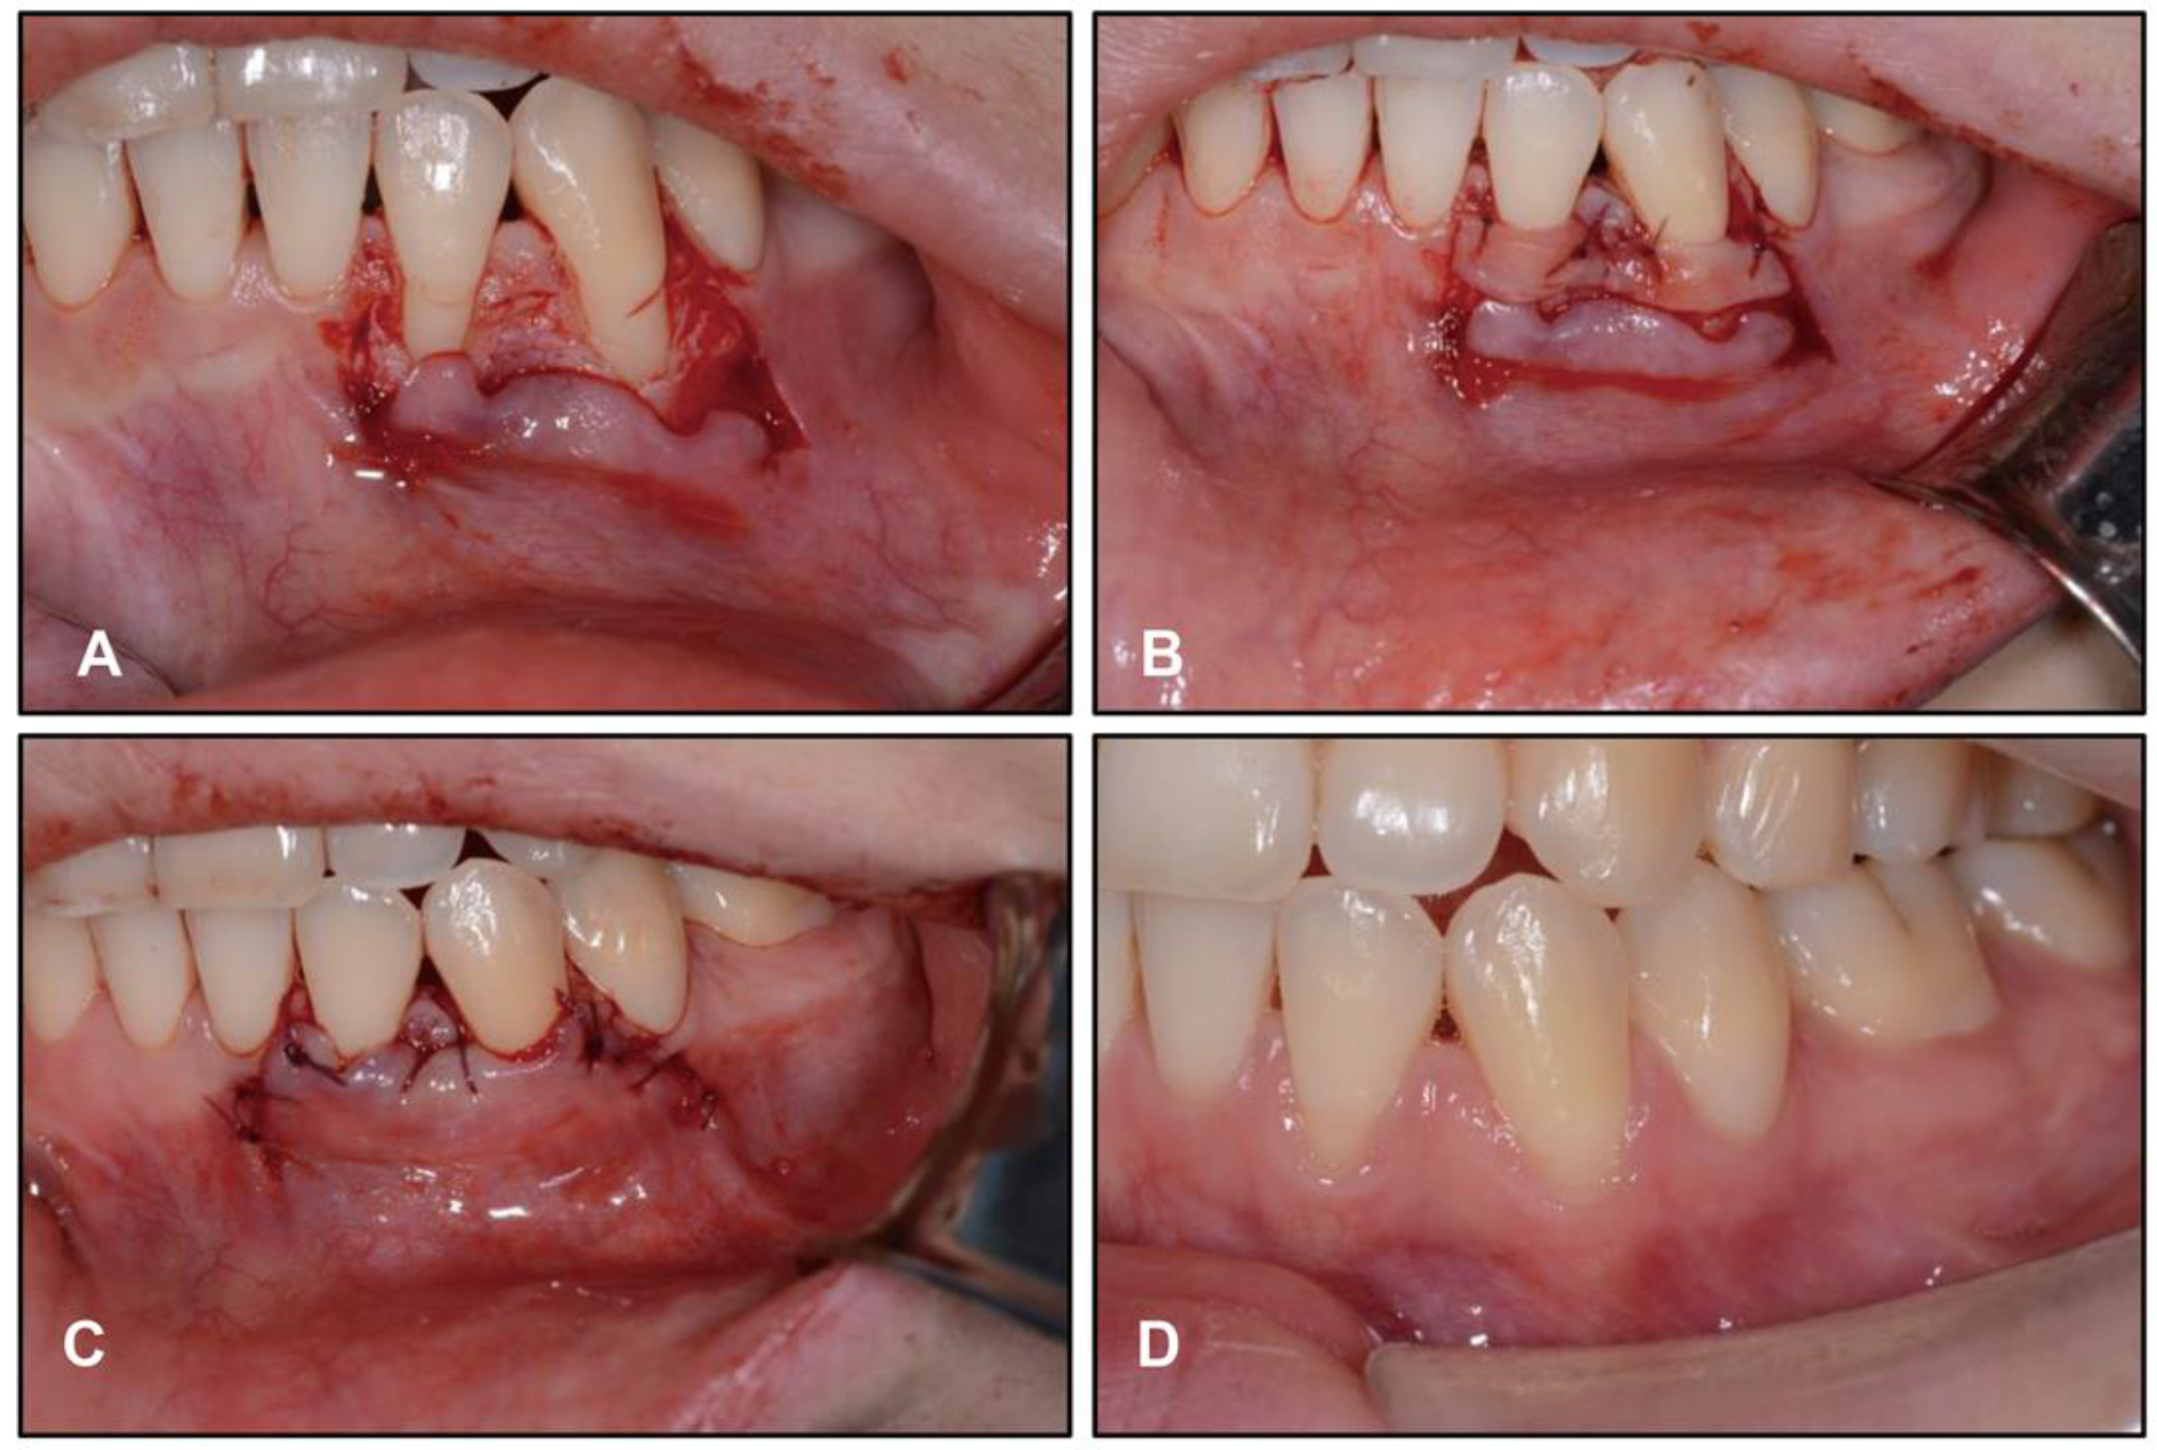

2.4. Treatment Progress

2.5. Treatment Results